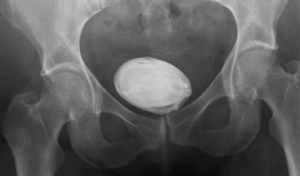

4. Bladder Stones

When we mentioned that Bladder infections occurred because of bacteria staying trapped inside the bladder… well, now imagine that when the urine is unable to be emptied, that concentrated urine will crystallize, form tiny minerals and eventually form into stones. Now, small bladder stones may pass without treatment, but sometimes bigger stones (like the one shown in the X-ray below) need treatment as these may lead to infections and other complications that may include:

a. Lower abdominal painb. Pain during urination

c. Frequent urination

d. Difficulty urinating or interrupted urine flow

e. Blood in the urine